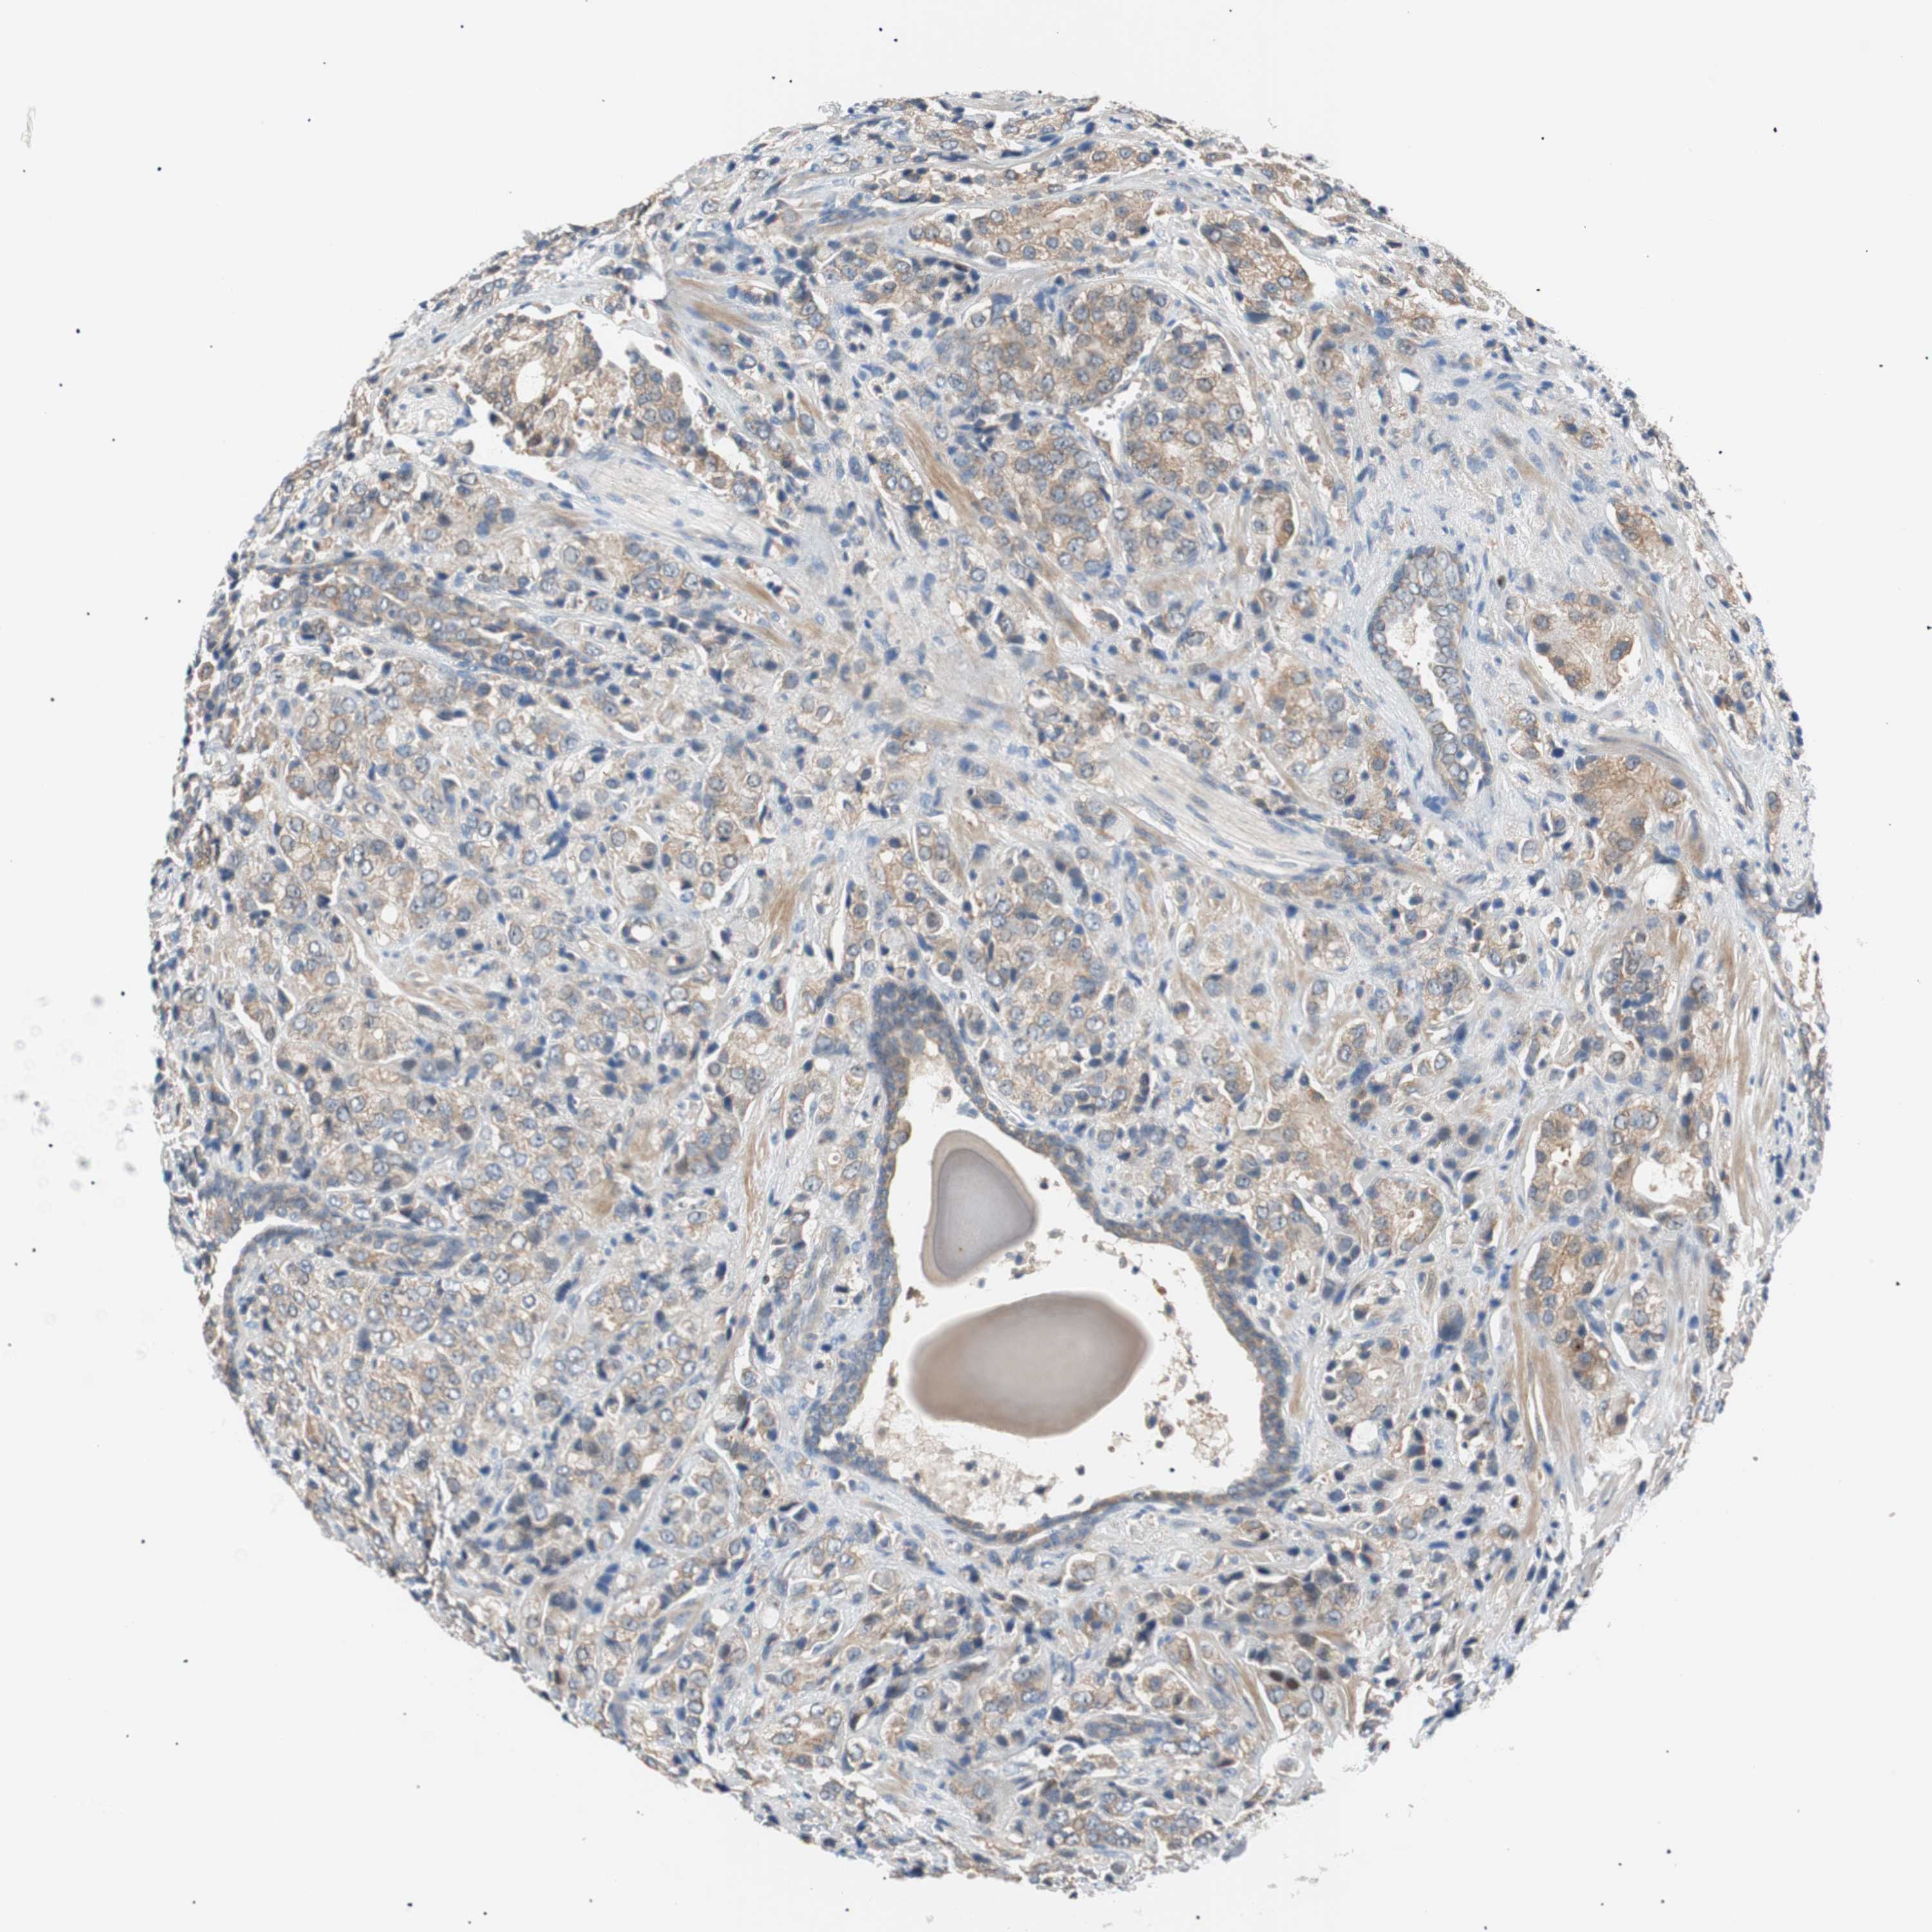

PROSTATE CANCER - Protein expressioni

A mouse-over function shows sample information and annotation data. Click on an image to view it in a full screen mode. Samples can be filtered based on level of antibody staining by selecting one or several of the following categories: high, medium, low and not detected. The assay and annotation is described here.

Antibody stainingi

Antibody staining in the annotated cell types in the current human tissue is reported as not detected, low, medium, or high, based on conventional immunohistochemistry profiling in selected tissues. This score is based on the combination of the staining intensity and fraction of stained cells.

Each image is clickable and will lead to virtual microscopy that enables deeper exploration of all samples and also displays staining intensity scores, fraction scores and subcellular localization as well as patient and tissue information for each sample.

Antibody HPA006277

Antibody HPA006507

Antibody CAB017027

Staining

High

Medium

Low

Not detected

Intensity

Strong

Moderate

Weak

Negative

Quantity

>75%

75%-25%

<25%

None

Location

Nuclear

Cytoplasmic/membranous

Cytoplasmic/membranous,nuclear

Adenocarcinoma, High grade

Adenocarcinoma, Low grade